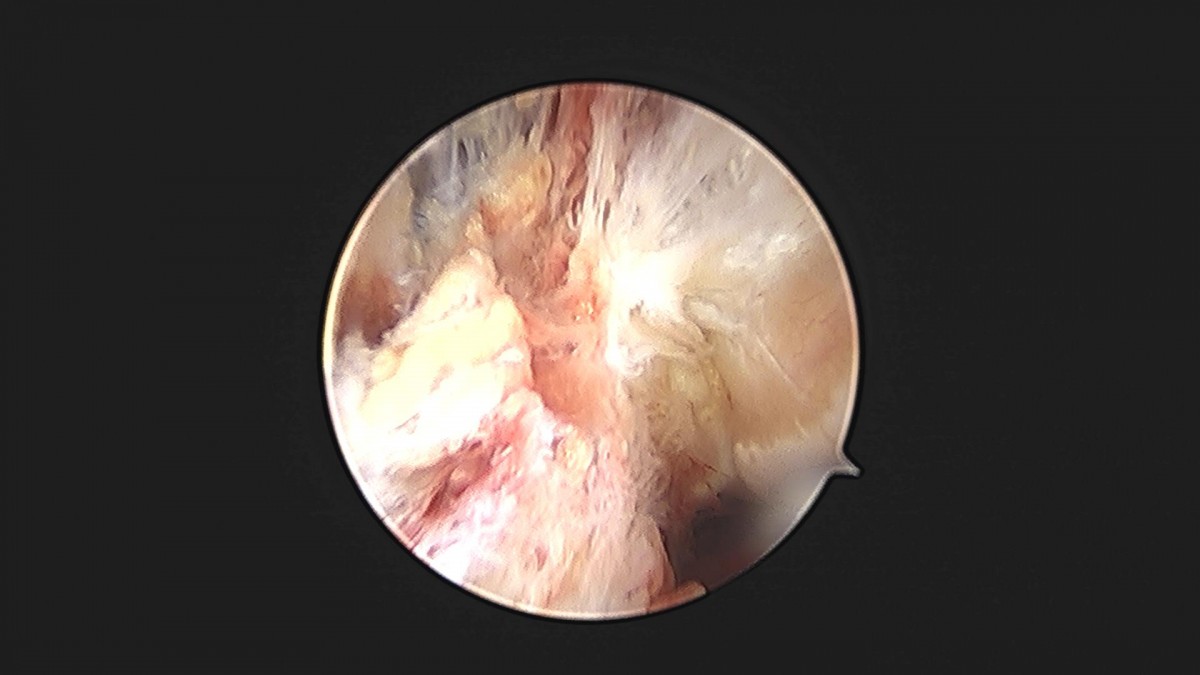

이재상원장님 발목 인대 봉합술 박지O 환자

작성자 최고관리자 댓글 0건 조회 860회 작성일 24-10-16 16:02